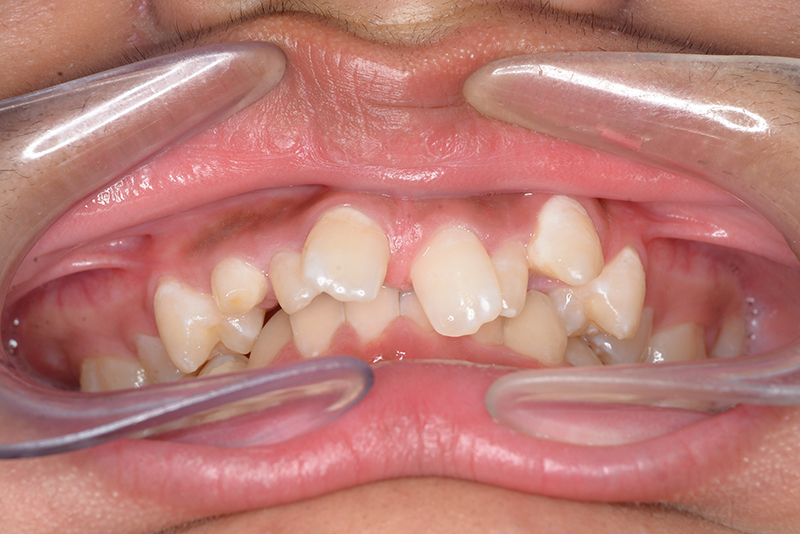

初診時

FP・IOP

主訴 すきっ歯 診断名 上顎右側犬歯先天欠如を伴うアングルⅡ級空隙歯列症例

初診時年齢 15歳5ヵ月 性別 動的治療期間 21ヵ月

口腔内所見 over jet 8.0mm、over bite 8.0mmで下顎歯列はスピー湾曲が強く、過蓋咬合、上突歯列、叢生歯列を呈しており、臼歯関係はⅡ級、左側7は鋏状咬合となっていた 。上顎両側2は矮小歯で上顎右側Cは晩期残存をしていた。また上顎歯列は空隙歯列を呈していた。